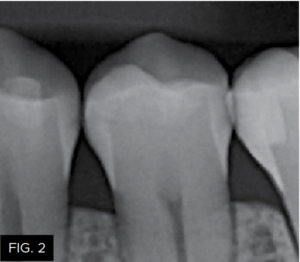

The patient shown in FIG. 1 presented with radiographic decay (FIG.2 and 3) on the distal surfaces of tooth numbers 19 (36) and 21 (34).